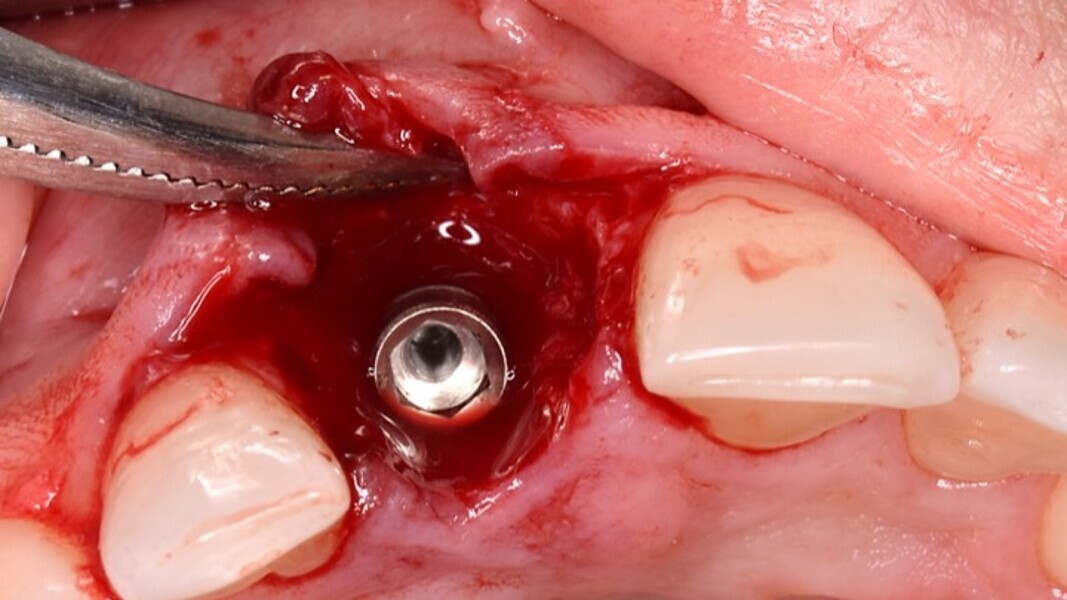

Figura 6. A pesar del defecto óseo, siempre buscamos la posibilidad de crear un nuevo alveolo quirúrgico que emerja por la zona del cíngulo de los dientes adyacentes, es decir, el margen de emergencia adecuado. En estos defectos, intentamos siempre el anclaje en profundidad con implantes largos de unos 16 mm debido al gran defecto existente. Es la única forma de que la estabilidad primaria del implante permita realizar una Prótesis Inmediata.

Figura 7. Implante de conexión interna insertado 2 mm por debajo de la cresta ósea, independientemente del defecto existente y a 55 Nw. Al no existir margen vestibular, tomamos como referencia los dos picos óseos de las papilas y entre ellos trazamos una línea imaginaria que los una enterrando el hombro unos 2 ó 3 mm por debajo de ella.